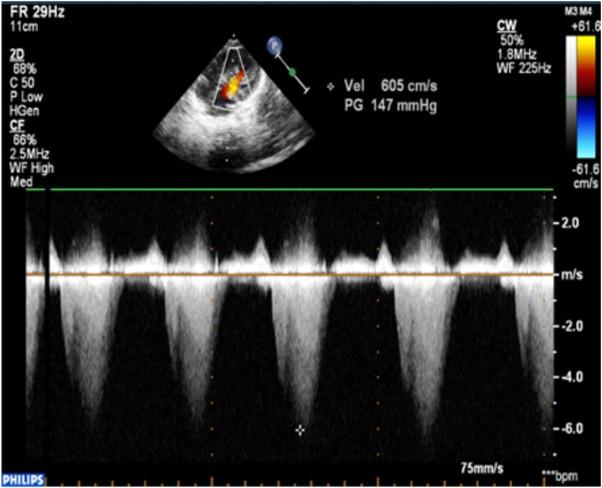

2D, color and continuous-wave Doppler echocardiography showed obstructive hypertrophic cardiomyopathy (OHCM) predominantly in the septal region (Fig. 2, 3), pulmonary infundibular and valvular stenosis as well as a small ASD with a left to right shunt.

Continuous-wave Doppler apical 4 chambers view: hypertrophic cardiomyopathy predominantly septal with continuous-wave Doppler with a peak gradient in LVOT of 147 mmHg (LVOT-left ventricular outflow tract)